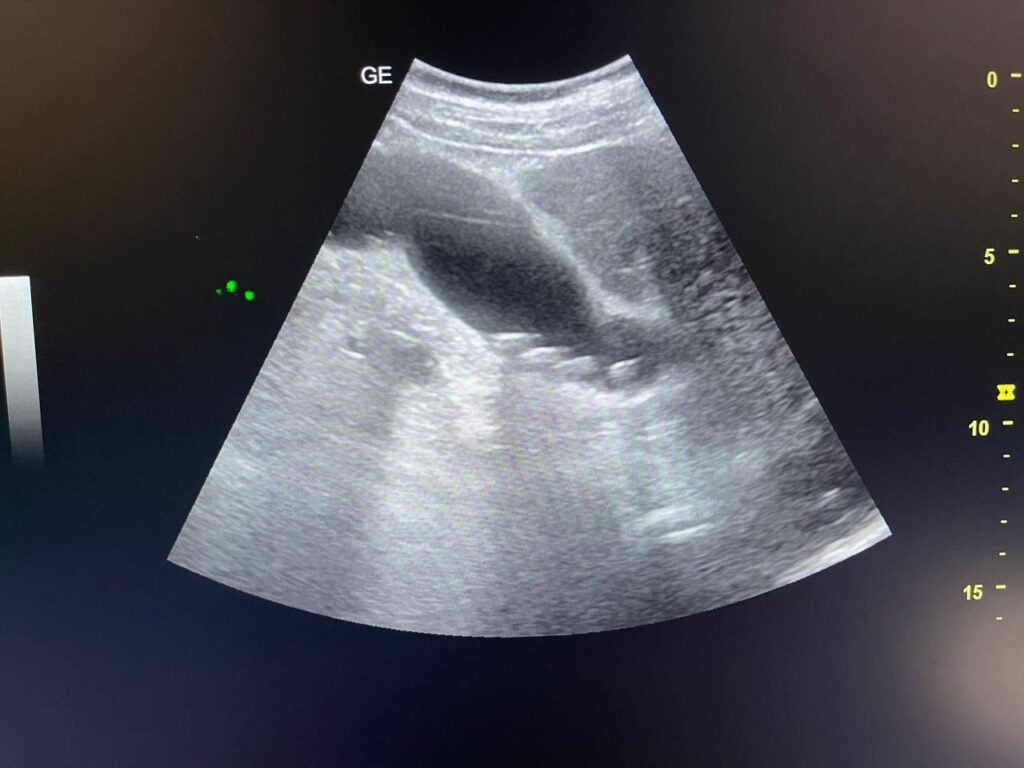

GB STONES & CBD STONE

Gall bladder distended,  increase wall thickness 5.5mm edematous, contain multiple mobile stones of variable sizes , the largest 12mm + dilated common bile duct 13mm , due to presence of stone about 25mm in the distal part